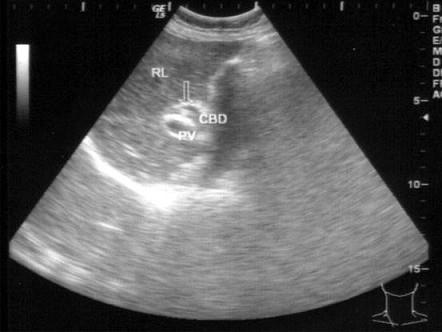

问题 患者女32岁,右上腹剧烈疼痛3小时就医,体检无发热,上腹痛叩击痛(弱阳性)。B超检查如图所示,根据超声声像图,诊断为?(?)

选项 A.胆总管癌 B.胆总管结石 C.胆总管胆泥淤积 D.胆总管蛔虫 E.胆总管内引流管回声

答案 D